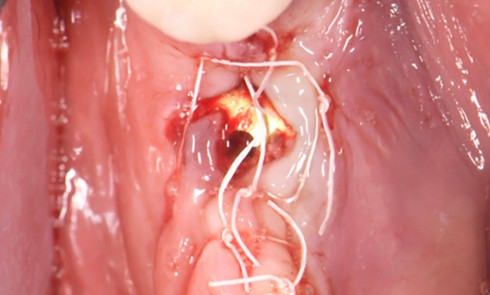

La patiente 61 ans Sous bêta-bloquant Bonne hygiène orale Parodontite traitée et stabilisée depuis 2016 Maintenances tous les 6 mois...